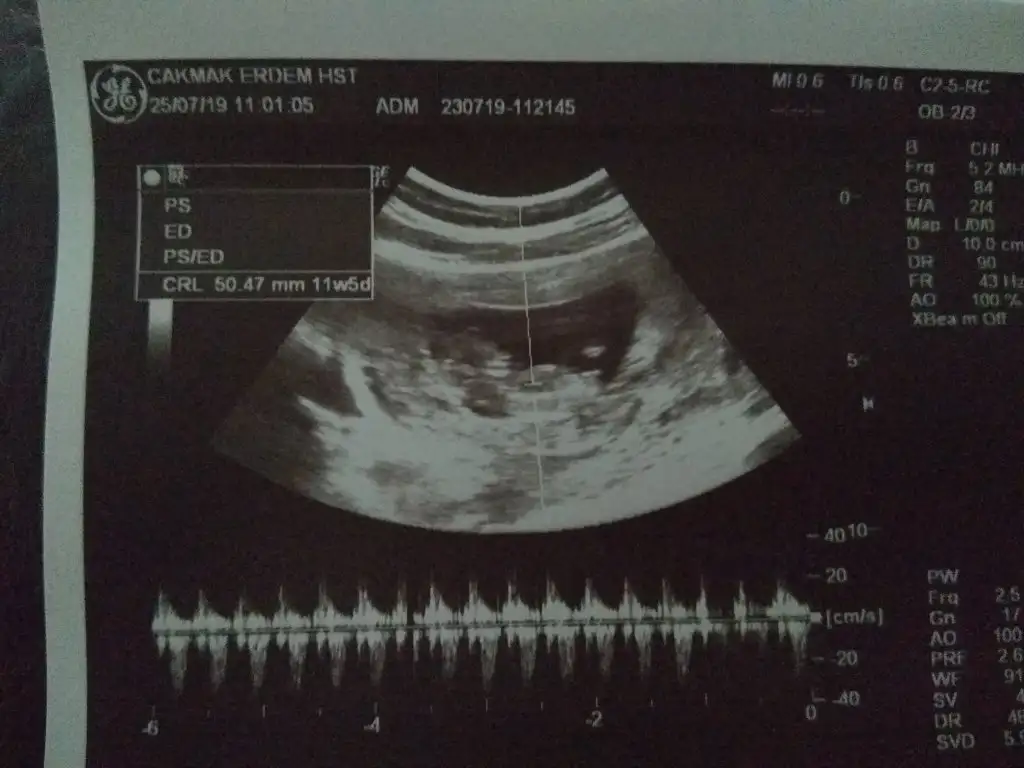

Erkek gibiHanımlar merhaba benim bebeğime de bakar mısınız sizce kız mı erkek miEki Görüntüle 2292836

Erkek bebişHanımlar merhaba benim bebeğime de bakar mısınız sizce kız mı erkek miEki Görüntüle 2292836

Erkek gibi

teşekkür ederim ben hiç anlamıyorum gerçekten eşimle başından beri erkek hissediyoruz ama dün bir baktım kız mı acaba dedim erkek dediniz Rabbim sağlıkla kavuştursunErkek bebiş

Kizzz :)Hanımlar merhaba benim bebeğime de bakar mısınız sizce kız mı erkek miEki Görüntüle 2292836